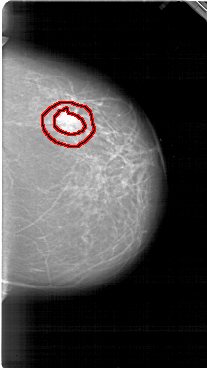

FILE: A_1950_1.RIGHT_MLO.OVERLAY

TOTAL_ABNORMALITIES 1

ABNORMALITY 1

LESION_TYPE MASS SHAPE IRREGULAR MARGINS SPICULATED

ASSESSMENT 5

SUBTLETY 5

PATHOLOGY BENIGN

TOTAL_OUTLINES 1

BOUNDARY